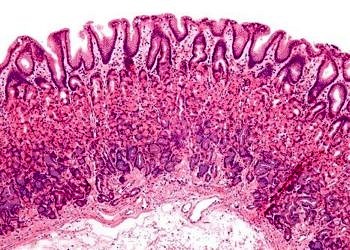

Kolera vibriyonlarıyla oluşan, şiddetli ishal, kusma ile karakterize, epidemi ve pandemilere sebep olan GİS’ in akut bir infeksiyon hastalığıdır. Dehidratasyon,...